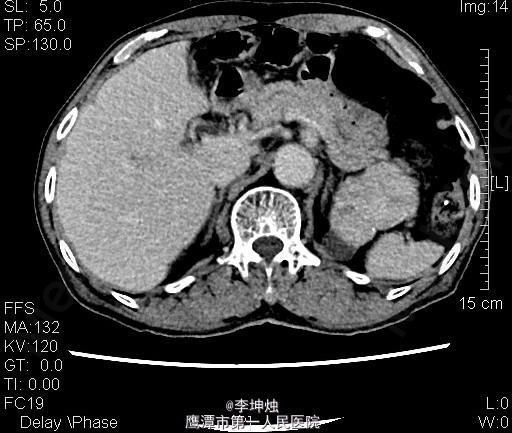

3、查体:增加腹压或站立位时右侧腹股沟隆起,可触及一大小约4*5cm肿物,可进入同侧阴囊,质软,边界清,无压痛,压迫肿物表面后嘱患者咳嗽,有冲击感,平卧或用手可将肿物回纳腹腔。直肠指检:肛门括约肌稍松弛,前列腺明显增大,大小约:3×4cm,表面光滑,质韧,边缘清楚,中央沟变浅,未触及明显结节,指套未见染血。 4、辅助检查:当地人民医院,腹部CT提示考虑左肾Ca可能;慢性膀胱炎;右侧腹股沟区见肠管嵌如;前列腺增生。我院双肾CT平扫+增强:左肾上极肿块,考虑肾癌,侵犯左肾上部皮髓质及左肾上盏,可疑侵及胰尾部。

5、诊断:左肾占位,左肾ca? 6、处理:入院完善相关检查,核素肾动态显像:双肾灌注轻度降低、功能中度受损。双肾+肾上腺CT:左肾上极肿块,考虑肾癌,侵犯左肾上部皮髓质及左肾上盏,可疑侵及胰尾部。排除手术禁忌后,行“腹腔镜下左肾根治+肾门淋巴结清扫术”,术后予“头孢哌酮钠舒巴坦钠(舒普深)”抗感染、抑酸、营养补液等处理,术后恢复可。病理提示嗜酸性细胞瘤。

7、肾嗜酸细胞瘤病因目前不明确,患病年龄与肾透明细胞癌相似,影响学结果相似,大多数患者的影像学检查结果很难与肾透明细胞癌相区别,由于部分患者肿瘤中央部有放射状疤,可以通过CT或MRI检查发现肿瘤中央星状瘢痕可为诊断本病提供帮助。确诊需依靠手术后病理检查。怀疑是肾嗜酸细胞瘤时,肿瘤大小和部位不影响保留肾单位手术,但由于术前多数患者不能被明确诊断,往往被误诊为肾癌而实施了根治性肾切除术。